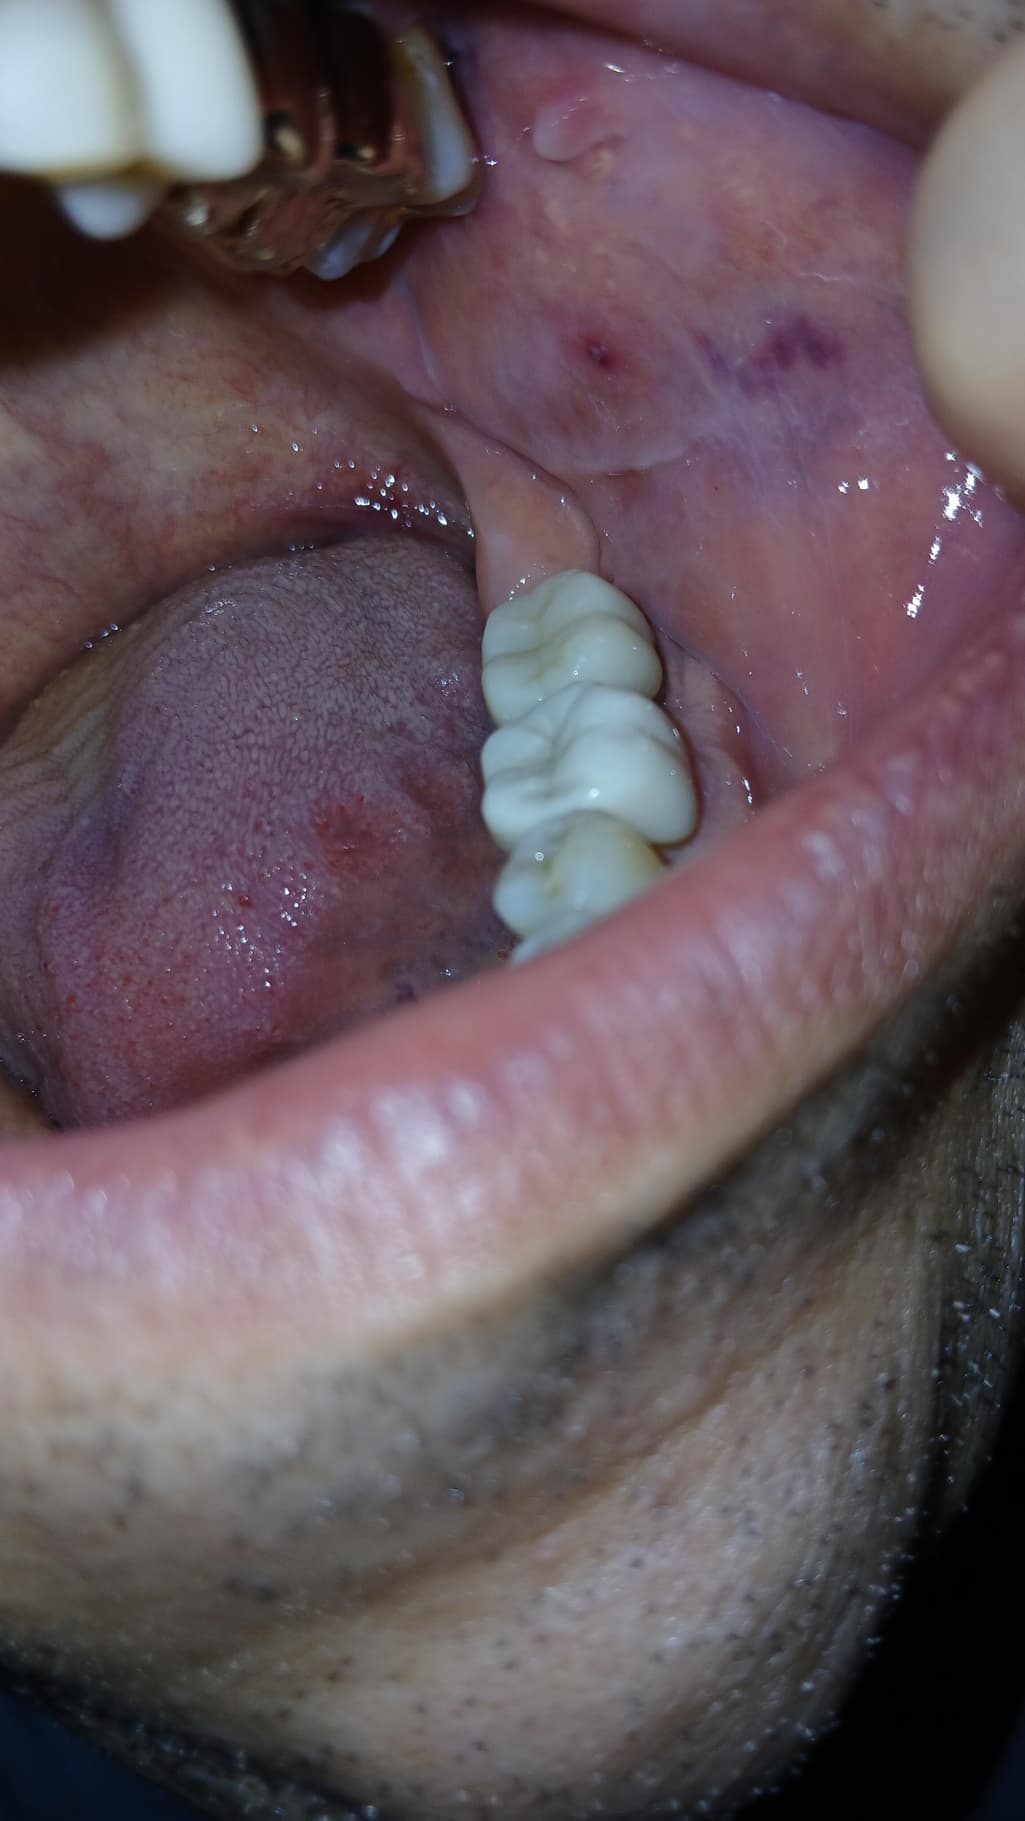

갑자기 입안볼점막에 사진과같이 붉은상처인지 볼점막에 피멍이 들어있습니다

음식을 먹다가 씹어서 그런걸까요? 전혀아프지않아요

입안 볼 점막에 생긴 피멍 자국은 여러 원인으로 발생할 수 있습니다. 음식을 먹다가 볼을 씹는 경우, 혈액 응고 장애, 약물 부작용, 또는 특정 질환의 증상일 수도 있습니다. 현재 복용 중인 항바이러스제나 기저 질환인 간경화도 관련이 있을 수 있으므로, 정확한 원인을 파악하기 위해 병원을 방문하여 진료를 받아보시는 것이 좋겠습니다.

특히 간경화 환자분들은 혈액 응고 기능에 이상이 생길 수 있으므로, 출혈 경향이 높아질 수 있습니다. 따라서, 현재 상태에 대해 담당 의사 선생님과 상담하여 필요한 검사를 받고, 적절한 조치를 취하는 것이 중요합니다. 불편함이 없더라도, 추가적인 문제가 발생하지 않도록 꼭 전문가의 진료를 받아보시길 권유드립니다.